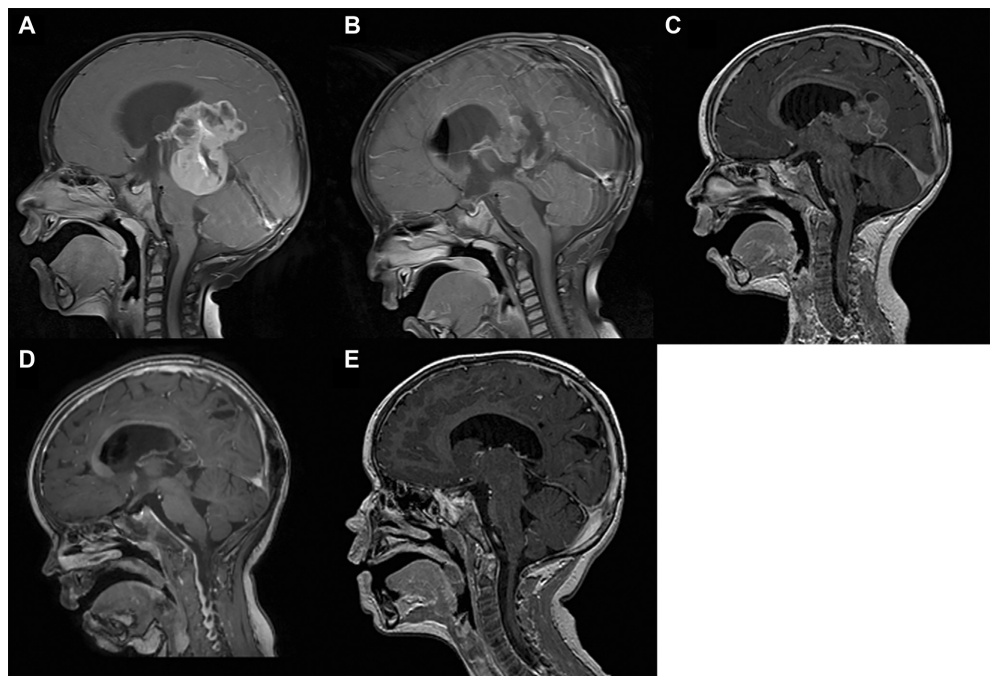

我们还对儿童PTPR病例报告进行了多方位的文献综述,同时描述了这一人群中新的实体的当前管理。病例介绍1例3岁男童,2级PTPR,入院复查。9个月前,患者因急性脑积水而在国外接受病灶次全切除。后续的脑磁共振成像(MRI)显示持久性的较大增强的松果体区损害和一个小囊性成分(图1)。脑室扩大也存在。患者无神经功能缺损。通过枕半球间入路行全肿瘤切除术,患者坐位(图1)。术后病程平稳。

图1:矢状脑磁共振成像(MRI)。(A和B)术前MRI显示松果体病变(A),已在国外接受过次全切除(B)。组织学诊断为松果体区II级乳头状肿瘤。(C) 9个月时MRI显示肿瘤再生。(D)患者在我科行枕半球间入路全切除,随后行辅助放化疗。组织学检查显示肿瘤进展(WHO III级)。(E)术后3年多患者病情持续良好,没有复发迹象。基于手术视频分析,我们强调了以下显微外科方面:

术后组织学诊断为III级PTPR。免疫组化分析显示,病变呈全角蛋白(CK5、CK6、CK8和CK18)、波形蛋白、微管相关蛋白2、S100蛋白、整合酶互作物1、CD99、转thyretin、CD56、上皮膜抗原(EMA;和突触素(弱病灶阳性)。另一方面,病变中神经丝蛋白、胶质纤维酸性蛋白(GFAP)和嗜chromogranin A呈阴性(图2)。MIB-1增殖指数为25%,有丝分裂特异性标记物磷酸组蛋白h3在15个有丝分裂细胞/mm2时被检测到。与一开始手术的组织学结果相比,肿瘤复发具有更多的坏死、更多的有丝分裂和更高的MIB-1增殖指数。术后4周,患者接受松果体肿瘤床局部分割放射治疗。总剂量54戈瑞除以日剂量1.8戈瑞。2015年2月,患者开始接受顺铂-环磷酰胺脒-依托泊苷静脉化疗,4个周期,每个周期21天:1)前3个周期1,8,15天:长春新碱1.5 mg/m2;2)1、2、3天:依托泊苷100 mg/;3)1天,顺铂100 mg/m2;4)2天和3天:环磷酰胺1000 mg/m2.4由于患者先天性畸形有1个肾,顺铂剂量由100 mg/m2降至80 mg/m2。术后3年多,患者临床表现良好,无发育迟滞和复发迹象(图1)。